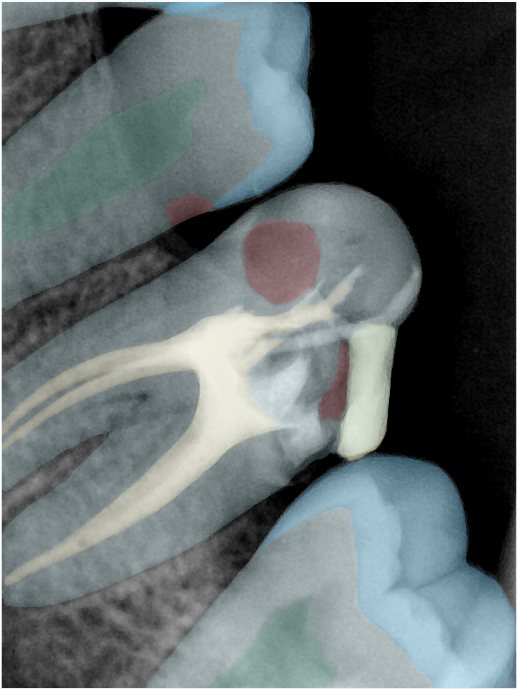

CR/DR 牙齿分割阶段记录

当前进展

- 完成了 CR/DR 牙齿相关分割训练

- 当前结果已经达到阶段预期,但仍有细节问题需要继续处理

相关测试

遇到的问题

- 训练过程中出现过 mask 下移问题

- 部分结果会出现 box 填充异常

- mask 边缘仍然有比较明显的锯齿感